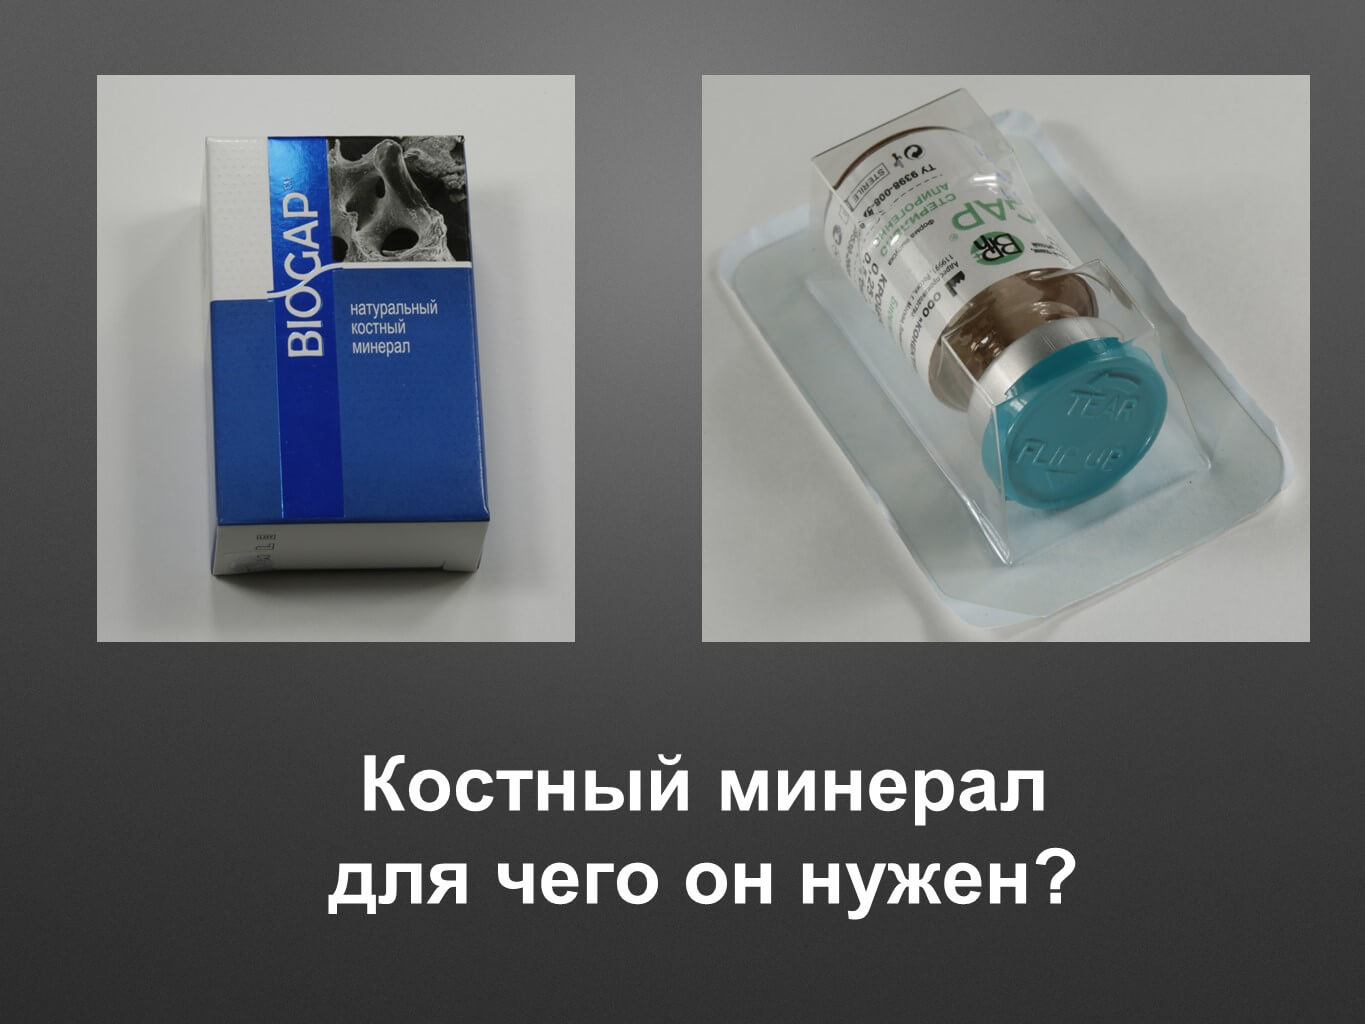

Костный минерал – «золотой стандарт» в современном мире костных материалов

Костный минерал – «золотой стандарт» в современном мире костных материалов

Прочитав эту статью, вы подробно познакомитесь с нашим продуктом Биоимплант ГАП, который представляет из себя костный минерал. Вы узнаете для чего он нужен и что получается из костного минерала. Также в статье представлена сравнение структуры костного минерала Биоимплант ГАП и другого костного минерала швейцарского производителя, на основе серии микрофотографий.